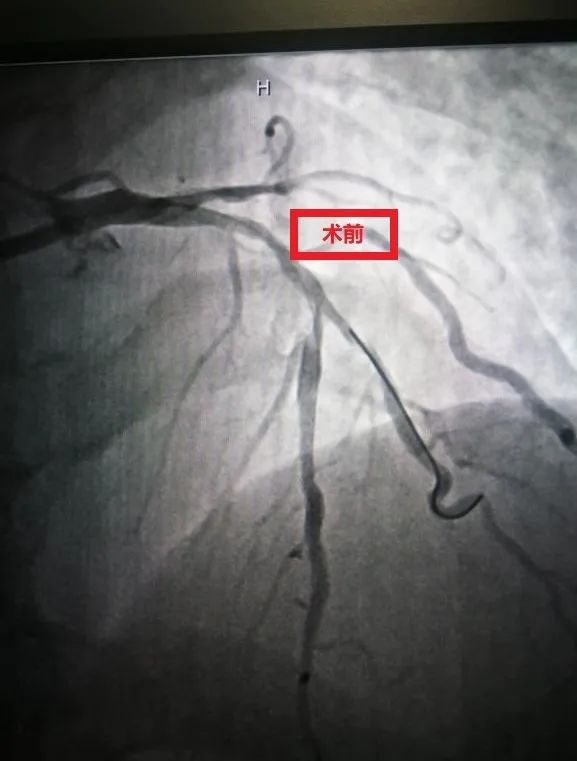

第一次术前

第一次术后